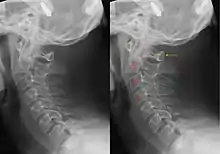

Hangman's fracture is the colloquial name given to a fracture of both pedicles, or pars interarticulares, of the axis vertebra (C2).

The mechanism of the injury is forcible hyperextension of the head, usually with distraction of the neck. Traditionally this would occur during judicial hanging, when the noose was placed below the condemned subject's chin. When the subject was dropped, the head would be forced into hyperextension by the full weight of the body, a sufficient force to cause the fracture. However, despite its long association with judicial hangings, one study of a series of such hangings showed that only a small minority of hangings produced a hangman's fracture.[4]

Although a hangman's fracture is unstable, survival from this fracture is relatively common, as the fracture itself tends to expand the spinal canal at the C2 level. It is not unusual for patients to walk in for treatment and have such a fracture discovered on X-rays. Only if the force of the injury is severe enough that the vertebral body of C2 is severely subluxed from C3 does the spinal cord become crushed, usually between the vertebral body of C3 and the posterior elements of C1 and C2.